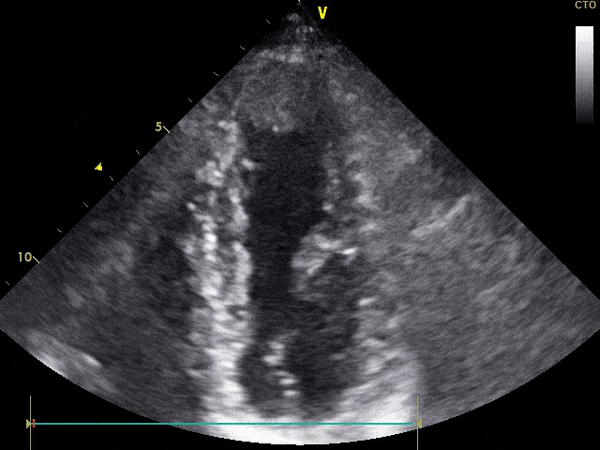

TTE

Ekokardiografi transtorakale triplex (2D, color, doppler) ose e njohur ndryshe si eko e zemrës, është e domosdoshme për të parë funksionimin e zemrës dhe lëvizshmërinë e mureve të saj.

Pamje të kapura me TTE: